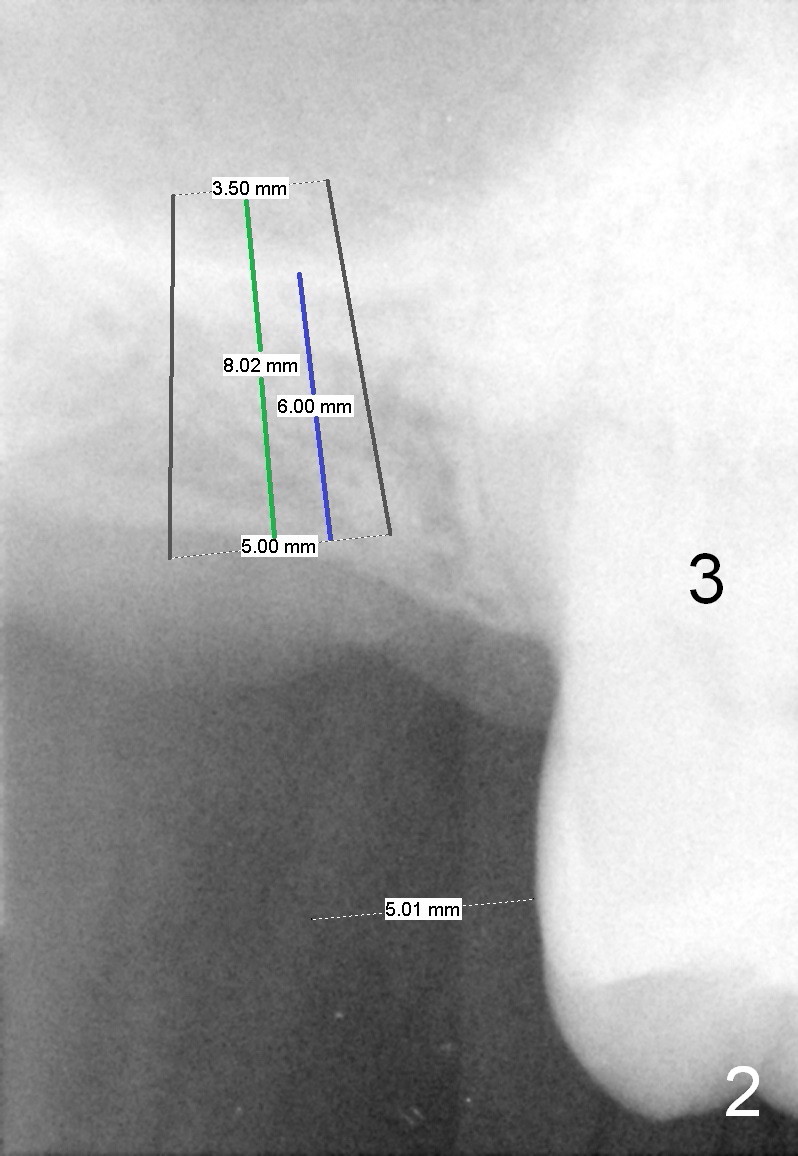

LJ will return for #2 implant placement 2 months post #31 implant placement.  Fig.1 was taken 2 years ago.  The tooth #2 had been supraerupted.  The bone height is apparently 7.5 mm (blue line), but with proper manipulation, there would be 14 mm bone available (green line) for placement of an immediate implant.  Fig.2 was taken a year post extraction.  The bone height is reduced to 6 mm (blue line).  With sinus lift, a 8 mm bone-level implant will be placed.

If the ridge is wide, use 4 mm tissue punch and 3 mm implant spacer (4/2+3=5mm) for access.  Otherwise, an incision is made.  Use a 2 mm pilot drill and 4 mm implant spacer to initiate osteotomy for 1-2 mm deep.  Then use a 3 or 4 mm trephine for less than 6 mm deep.  RT 2,3 or Bicon Osteotome (3.5 mm) will be used to lift the sinus floor.  Prepare Metronidazole, allograft and Osteogen.